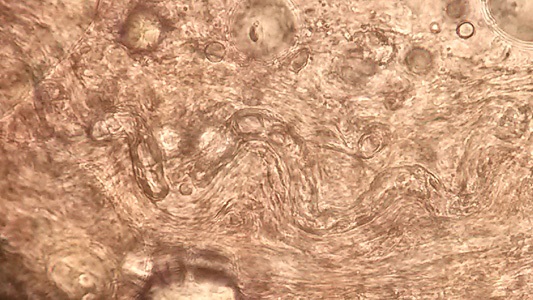

December 2018

DPDx is an educational resource designed for health professionals and laboratory scientists. For an overview including prevention, control, and treatment visit www.cy118119.com/parasites/.